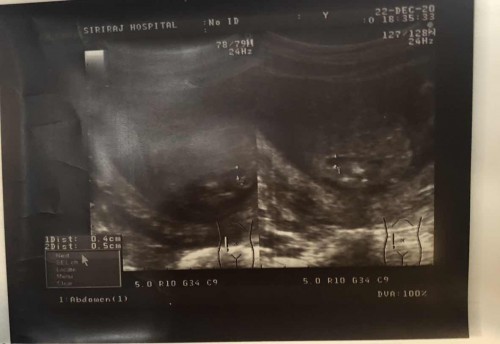

ทารกในครรภ์มีภาวะไตโต

น้องอายุครรภ์ 20 w ไตข้างนึง 4 mm อีกข้าง 5 mm หมอบอกไตน้องโตใครมีปัญหานี้บางครับ #ขอคำแนะนำครับ

บ้านนี้เจอเหมือนกันค่ะ 19 WK โตมี 4 มิลกว่านิดๆ หวังว่า อายุครรภ์เพิ่มขึ้นจะหายเองค่ะ